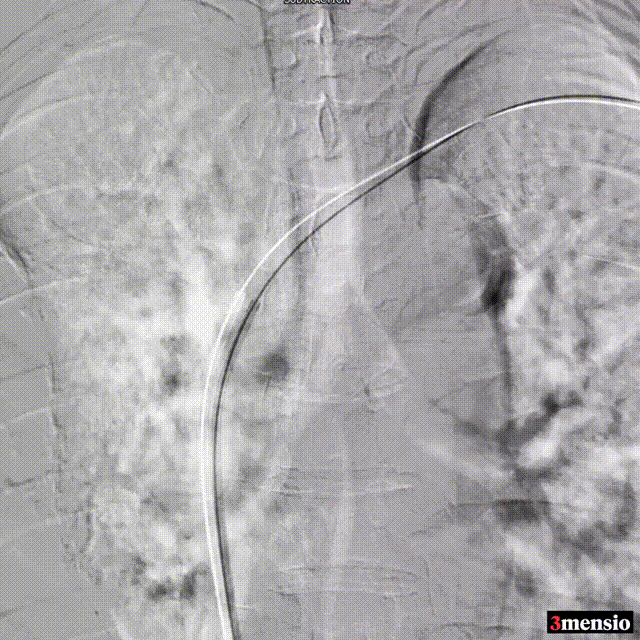

图:造影证实左侧头臂干静脉闭塞

图:球囊扩张左侧头臂干静脉闭塞段

图:左侧头臂静脉完全通畅